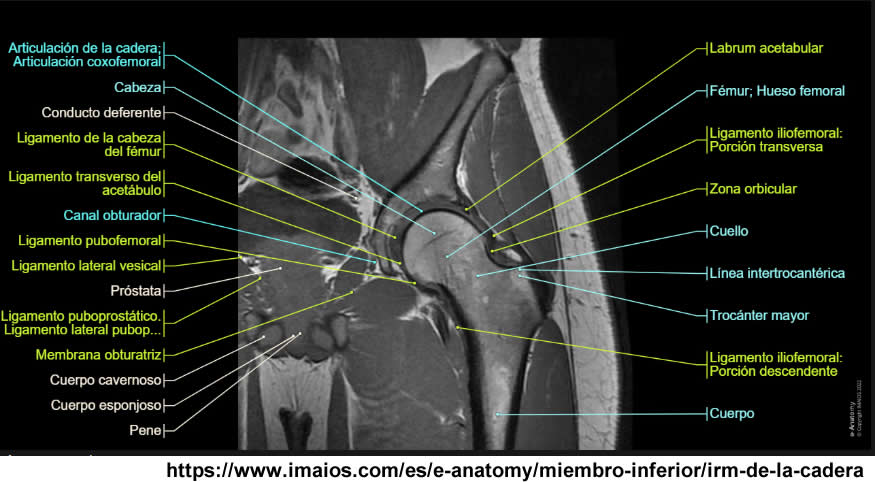

Se realiza estudio de resonancia magnética con un equipo de 1.5 tesla, se aplica protocolo de sedación, se utiliza bobina fase arrays, y se procede a adquirir un PSP, en tres planos, secuencias Se, ponderadas a T1 y T2, se administra medio de contraste por vía I.V.